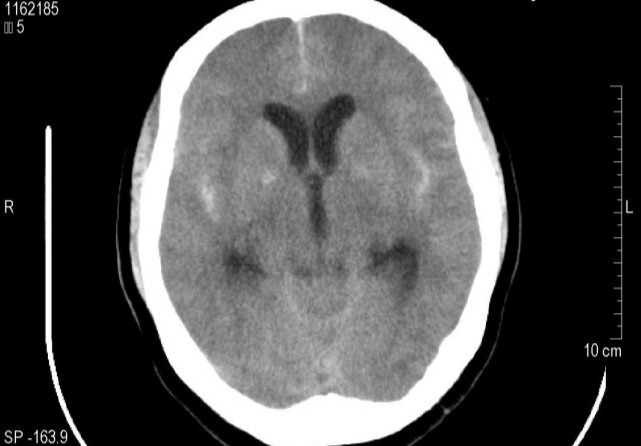

一、诱发中风。

高血压是诱发中风的高危因素。研究表明:高血压患者中风的发生率是正常血压的7.76倍。如果高血压得到很好的控制,那么患中风的概率降低40%,患冠心病的概率降低15%。所以高血压本身并不可怕,可怕的是并发症。如果你血压偏高,一定要引起重视,积极控制。